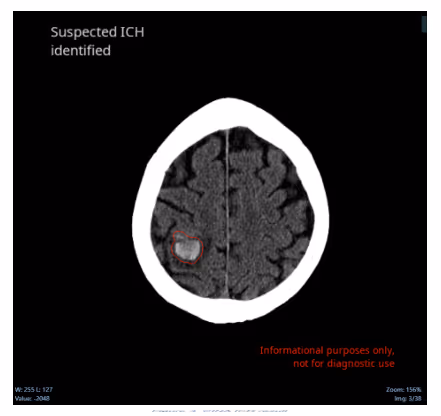

Ferrum Health partners with best-in-class AI providers offering solutions designed to reduce radiology workload and improve patient care.Avicenna Case Study: Improved Care CoordinationHow can CINA improve the coordination of patient care?IntroductionTimely and accurate diagnoses are necessary for the management of acute ICH patients. Unfortunately, 16% of critical findings are never reported to referring clinicians. This drop-in communication intuitively impacts patient care, especially for those with ICH. For example, a subset of ICHs will go on to hemorrhagic expansion, which often occurs within the first 3-4.5 hours of symptom onset.Clinical CaseA 60-year-old patient arrived at the emergency department with left-hand weakness and vertigo. He began taking anticoagulant three days prior for a blood clot in his left leg. An NCCT was ordered and obtained urgently.

A little over two hours after imaging acquisition, the radiologist reviewed the case and report a 1.8 cm acute intraparenchymal hemorrhage within the superior right frontoparietal region. Urgent neurosurgical consultation was recommended as well as further evaluation with MRI brain with and without contrast.

ConclusionCritical findings must be addressed without delay. However, report times for neuro-critical findings on head non-contrast computed tomography (NCCT) examinations can range from 1.5 to 4 hours. The CINA ICH mean time-to-notification is 22s. CINA-ICH drastically reduces the time to radiologist’s review and therefore coordination of care.Note: Segmentation is not currently available for clinical use in the United States. Please see Avicenna outputs documents for more information.Intracranial hemorrhages (ICH) affect over two million people worldwidewith a 40-50% patient mortality rate within one month, and 80% disability despite aggressive care.Quick and accurate early diagnosisof ICH mayfacilitate a prompt therapeutic response, allow fast decision-making, and ultimately improve outcomes.CINA-ICH uses deep learning to identify suspected intracranial hemorrhageand prioritizes those cases in the worklist, dramaticallyreducing turnaround time for head traumaand stroke patients.Interested in deploying CINA-ICH at your health facility? Contact the Ferrum Health team to learn more.